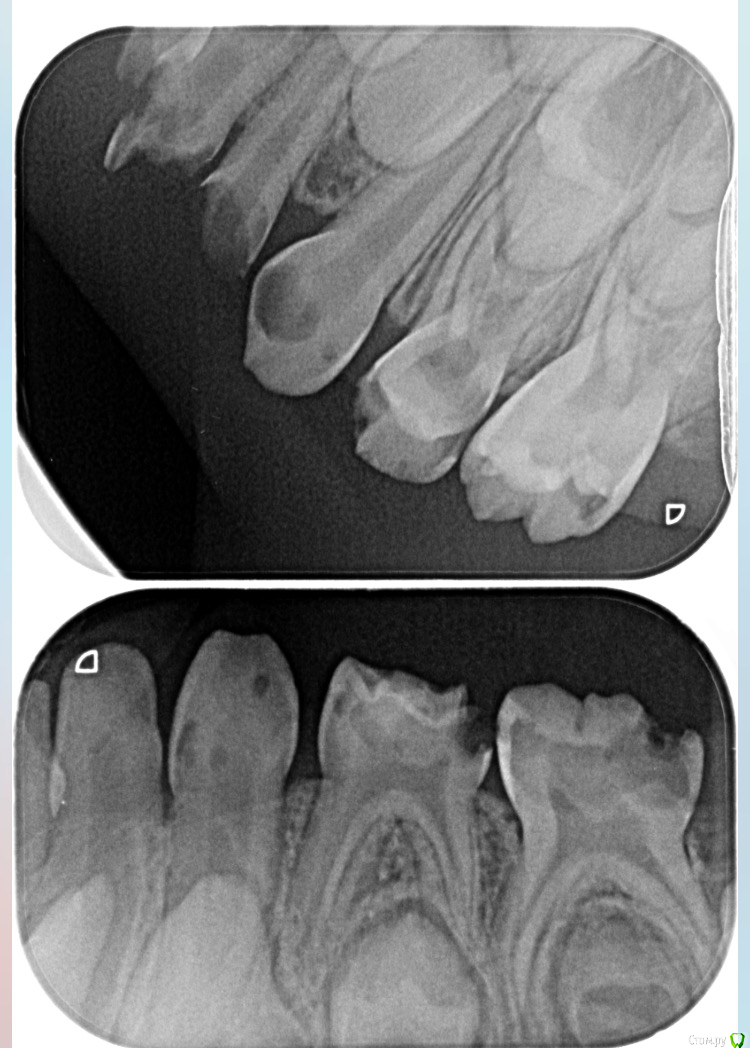

DAV86.06 Опубликовано 2 октября, 2017 Поделиться Опубликовано 2 октября, 2017 (изменено) Добрый вечер! Подскажите пожалуйста. Ребёнку 4года на жевательные зубки нижние предлагаютпоставить коронки. На сколько это актуально в нашем случае или можно обойтись пломбой? Изменено 2 октября, 2017 пользователем DAV86.06 1 Ссылка на комментарий

DAV86.06 Опубликовано 2 октября, 2017 Автор Поделиться Опубликовано 2 октября, 2017 Передние верхние зубы предлагают удалить тк лечить их смысла нет. И ещё нам насчитали 8 пульпитов♀ Ссылка на комментарий

ЕленаВалерьевна Опубликовано 2 октября, 2017 Поделиться Опубликовано 2 октября, 2017 с короночками будет надежнее, про пульпиты согласна с вашим доктором. по поводу передних зубов точно не могу сказать, только по снимку сложно ориентироваться, возможно и полечить получится. 1 Ссылка на комментарий